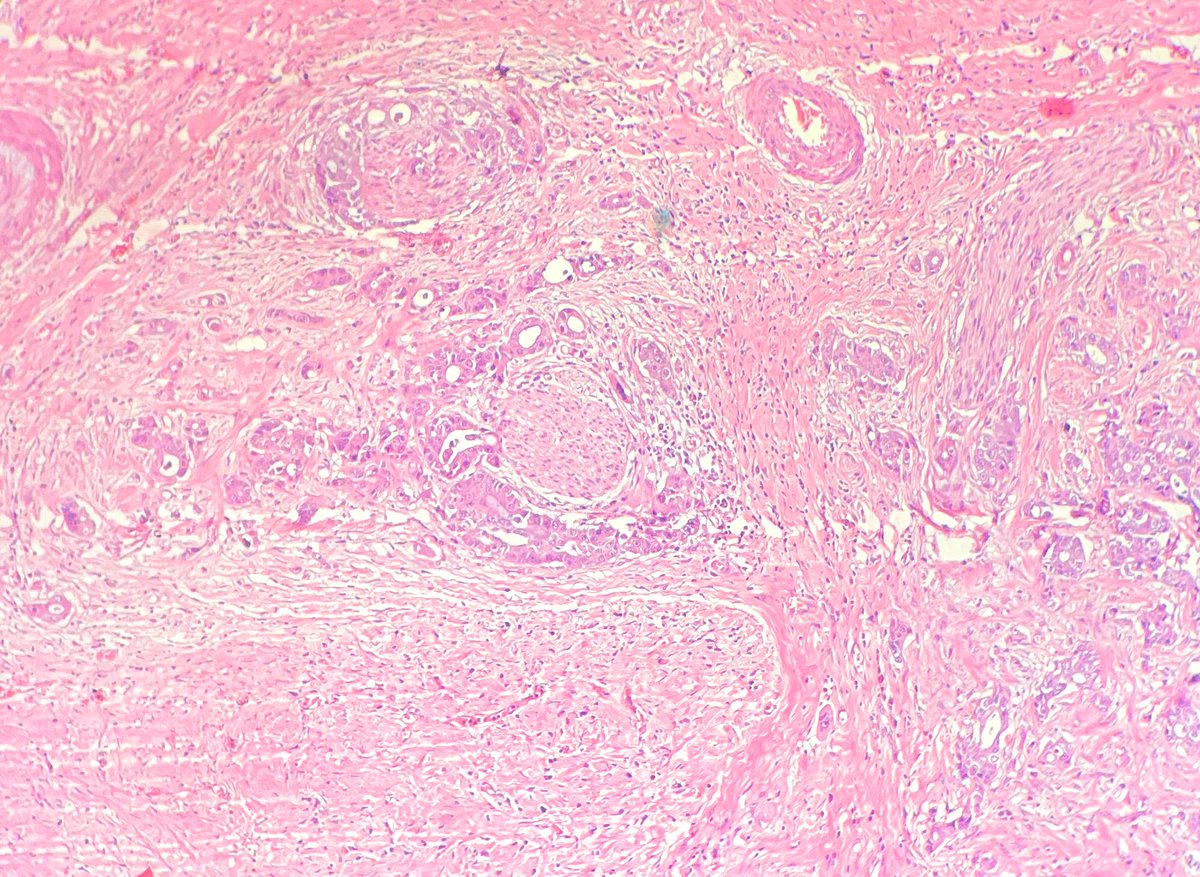

Bladder mass , different biopsies in the background of bilharzial cystitis #pathology #GUpath #twitterpath

LFpath's tweet image. Bladder mass , different biopsies in the background of bilharzial cystitis #pathology #GUpath #twitterpath